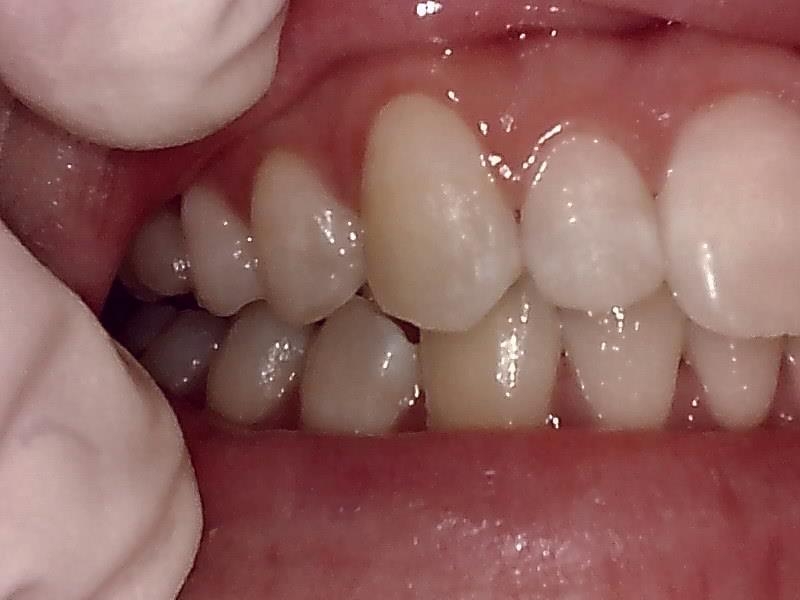

右側